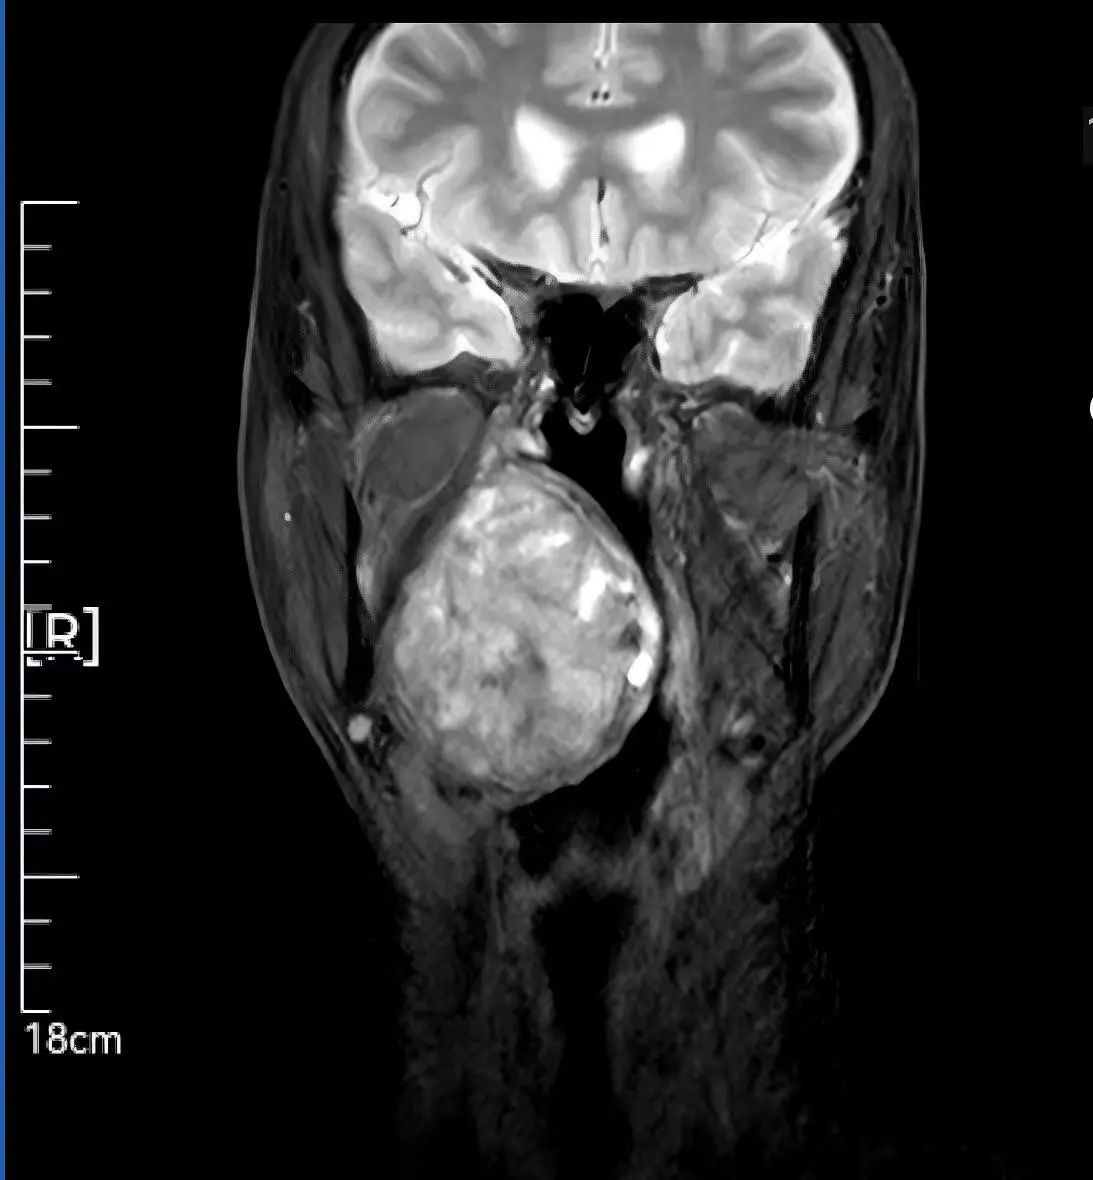

59歲患者因腭部膨隆伴吞咽呼吸困難輾轉(zhuǎn)求醫(yī),最終就診于我院頭頸外科。李智林副主任查體發(fā)現(xiàn),患者咽部明顯膨隆,懸雍垂左偏,雙側(cè)扁桃體完全被腫瘤遮蔽,口咽腔嚴(yán)重狹窄移位。影像檢查顯示,6.2×1.4×7.3cm的腫瘤深居右側(cè)咽旁間隙,穿刺病理提示,明確為涎腺來源多形性腺瘤,毗鄰頸動(dòng)脈、顱底神經(jīng)群,手術(shù)風(fēng)險(xiǎn)極高。

顯微操作實(shí)施“咽喉拆彈” 三階段方案守護(hù)神經(jīng)功能 面對(duì)“手術(shù)禁區(qū)挑戰(zhàn)”,團(tuán)隊(duì)制定精細(xì)化方案: 術(shù)前攻堅(jiān):利用MRI精準(zhǔn)定位腫瘤邊界,制定血管神經(jīng)保護(hù)預(yù)案; 術(shù)中突破:先行氣管切開建立生命通道,經(jīng)下頜骨劈開入路顯微分離腫瘤,完整保留頸內(nèi)動(dòng)脈、面神經(jīng)等重要結(jié)構(gòu); 功能重建:以鈦板固定下頜骨,最大程度恢復(fù)咀嚼功能與面部形態(tài)。 歷經(jīng)數(shù)小時(shí)顯微操作,最終實(shí)現(xiàn)了腫瘤的根治性完整切除,并奇跡般地完整保住了患者的局部核心結(jié)構(gòu)和重要神經(jīng)功能。 可視化溝通破疑慮 從“被動(dòng)治療”到“主動(dòng)共信” 面對(duì)下頜骨劈開的手術(shù)方案,患者對(duì)創(chuàng)傷及并發(fā)癥充滿擔(dān)憂。李智林副主任創(chuàng)新采用“模型+預(yù)案”可視化溝通模式,直觀演示手術(shù)路徑,并針對(duì)患者對(duì)切口美觀的需求優(yōu)化入路設(shè)計(jì)。通過“治療方案共決策”機(jī)制,患者全程參與診療討論,最終從“被動(dòng)接受”轉(zhuǎn)為“主動(dòng)信任”。術(shù)后,在護(hù)士長范改萍及病區(qū)護(hù)士長李霞護(hù)理團(tuán)隊(duì)的精細(xì)照料下,患者恢復(fù)良好,吞咽和呼吸功能逐漸改善,目前已順利康復(fù)出院。 “是你們給了我第二次生命,頭頸外科團(tuán)隊(duì)用技術(shù)解除我的病痛,用真誠治愈恐懼,這就是醫(yī)護(hù)最好的模樣。”這段樸實(shí)的感言,成為“技術(shù)救治+人文關(guān)懷”的最佳注釋。 學(xué)科引領(lǐng)賦能精準(zhǔn)醫(yī)療 技術(shù)與溫度并重的診療范式 此次手術(shù)由頭頸外科主任李德志教授全程指導(dǎo),依托科室多學(xué)科協(xié)作(MDT)體系與顯微外科技術(shù)優(yōu)勢,實(shí)現(xiàn)“精準(zhǔn)切除-功能保留-人文關(guān)懷”三重突破。未來,團(tuán)隊(duì)將以更前沿的醫(yī)療技術(shù)、更溫暖的人文關(guān)懷,不斷攀登醫(yī)學(xué)高峰,守護(hù)區(qū)域內(nèi)百姓頭頸健康,為生命安全構(gòu)筑堅(jiān)實(shí)防線。